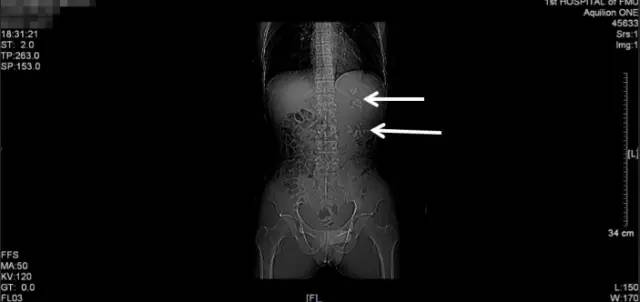

手术前KUB

术后复查KUB

通过本次术前术后的KUB对比,可以看到,经过这次手术,柯先生左肾的大部分结石已经消失了,仅剩下盏的一些小的结石。

可能有很多患者觉得结石手术是个很简单的手术,取干净结石并没有什么难度,有病人甚至认为有结石残留就是手术失败了!实际上这是个巨大的误区,临床上复杂肾结石一期取尽率文献报道在40-80%左右,我主刀完成的复杂鹿角形肾结石一期取尽率在80%以上,能将柯先生残留的结石处理干净,我也感到非常欣慰!